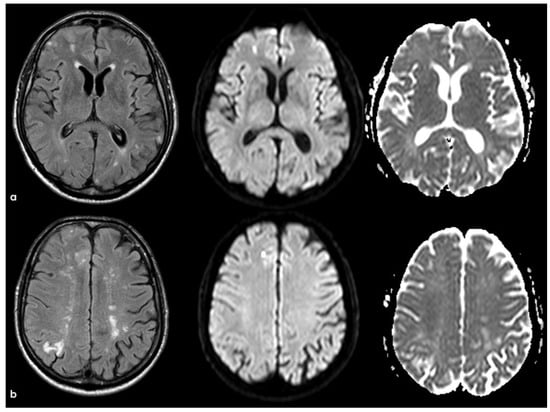

5. February 2017: First Recurrent CAA-Related Inflammation

6. December 2017: Recurrent SAH

7. April 2018: Second Recurrent CAA-Related Inflammation

8. April 2018: Third Recurrent CAA-Related Inflammation